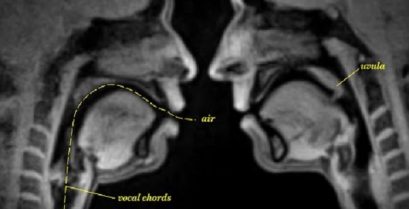

Menschlichen Lebens durch ein MRI-scanner

Im Gegensatz zu CT und Röntgen, Das MRT verwendet keine gefährliche Strahlung. Genauer gesagt, CT-Scans mit einem starken Magnetfeld und Hochfrequenzimpulse, die Wasserstoffprotonen zu manipulieren [...]